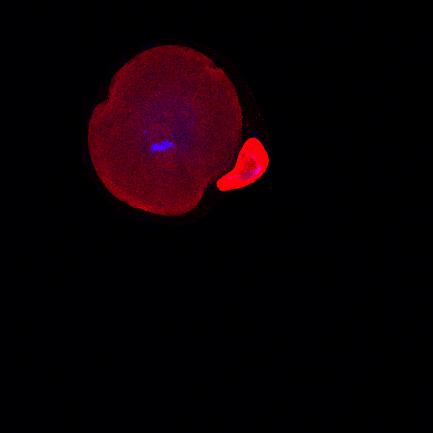

Obrazek 1: Mikromanipulační techniky otevřely možnost pro mnoho párů mít vlastní děti. Současné postupy však někdy nestačí, proto v rámci programu vyvíjíme nové bezpečné technologie.